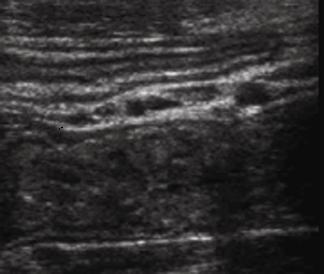

L'epaisseur de la paroi de

l'intestin est en moyen de 3mm avec des

plies muqueuses et de peristaltisme marquee .

Au ileon la hauteur des plies

muquese est diminue et espace entre des plies

muqueuse sont augementes |

Jejunum : Important de

la presence de plissement de la muqueuse en

connivence |